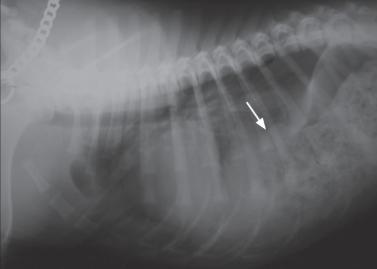

右侧胸片

通过体格检查后,依序进行影像学检查,分别是X射线检查、钡餐造影。

X光可显示肺部显影是否异常,肺部区域有没有被压迫的情况。